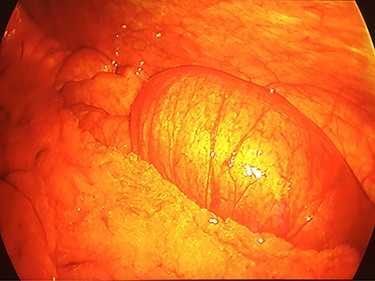

Intra-operative laparoscopic view of the intussuscepted small bowel prior to resection.

On exam, the patient was afebrile and tachycardic to 110 beats/minute. He appeared in acute distress but was oriented to person, place and time. His abdomen was non-distended but was rigid with severe abdominal pain with palpation in all four quadrants. Laboratory evaluation identified a leukocytosis to 16.5 K/mm3 with normal serum electrolytes and liver function tests. A CT was obtained, which showed a 4-cm segment entero-enteric intussusception without obstruction or signs of ischemia with non-specific bowel thickening proximal to the intussusception (Fig. 1). Given peritonitis on exam, the patient was taken to the operating room where the entero-enteric intussusception was identified and resected in bloc (Figs 2 and 3) No masses were palpated in the surgical specimen.